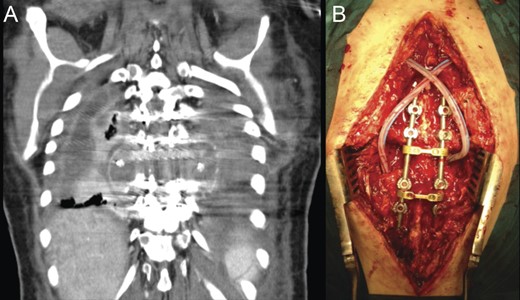

Due to the ongoing postoperative infection, a new operation was undertaken with surgical debridement of the infected tissues, allograft and titanium mesh extraction, which were replaced by iliac crest tricortical autograft for anterior support (Fig. 6). The posterior pedicle instrumentation was kept, after copious irrigation of the surgical wound. Drains were placed in the thoracic cavity and paravertebral spaces.

Revision procedure; a thoracotomy was performed for pus drainage and debridement, as well as removal of the anterior cage and allograft (A). A tricortical iliac bone autograft was used to maintain anterior-column stability (B). Postoperative radiographic study (C and D).

Blood cultures, as well as those from pus samples collected intraoperatively and from the explanted mesh and allograft identified Enterobacter aerogenes as the pathogenic agent. The same bacterium was isolated in a sample of allograft sent for cultures on the day of the index operation. A pathogen-directed course of i.v. antibiotic therapy was initiated.